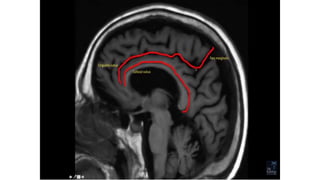

SULCI & GYRI

SULCUS IS THE DEPRESSION [VALLEYS]

AND

GYRUS IS THE RIDGE [HILLS]

Fissure/sulcus Importance

• Interhemispheric fissure • Separates two lobes

 Sylvian fissure/ Lateral

Sulcus

 Frontal to temporal

 Central sulcus  Frontal to parietal

 Callosal sulcus

 Cingulate sulcus

 Interparietal sulcus

 Parieto occipital sulcus

 Calcarine sulcus

Interhemispheric fissure

The central sulcus-The sigmoid hook

The pars bracket sign- Parieto occipital sulcus

Fish tail- parieto occipital sulcus

Pars marginalis

The bifid sulcus

The intraparietal sulcus